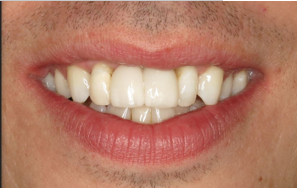

Before And After

The patient has a high lip line and aesthetic outcome was important